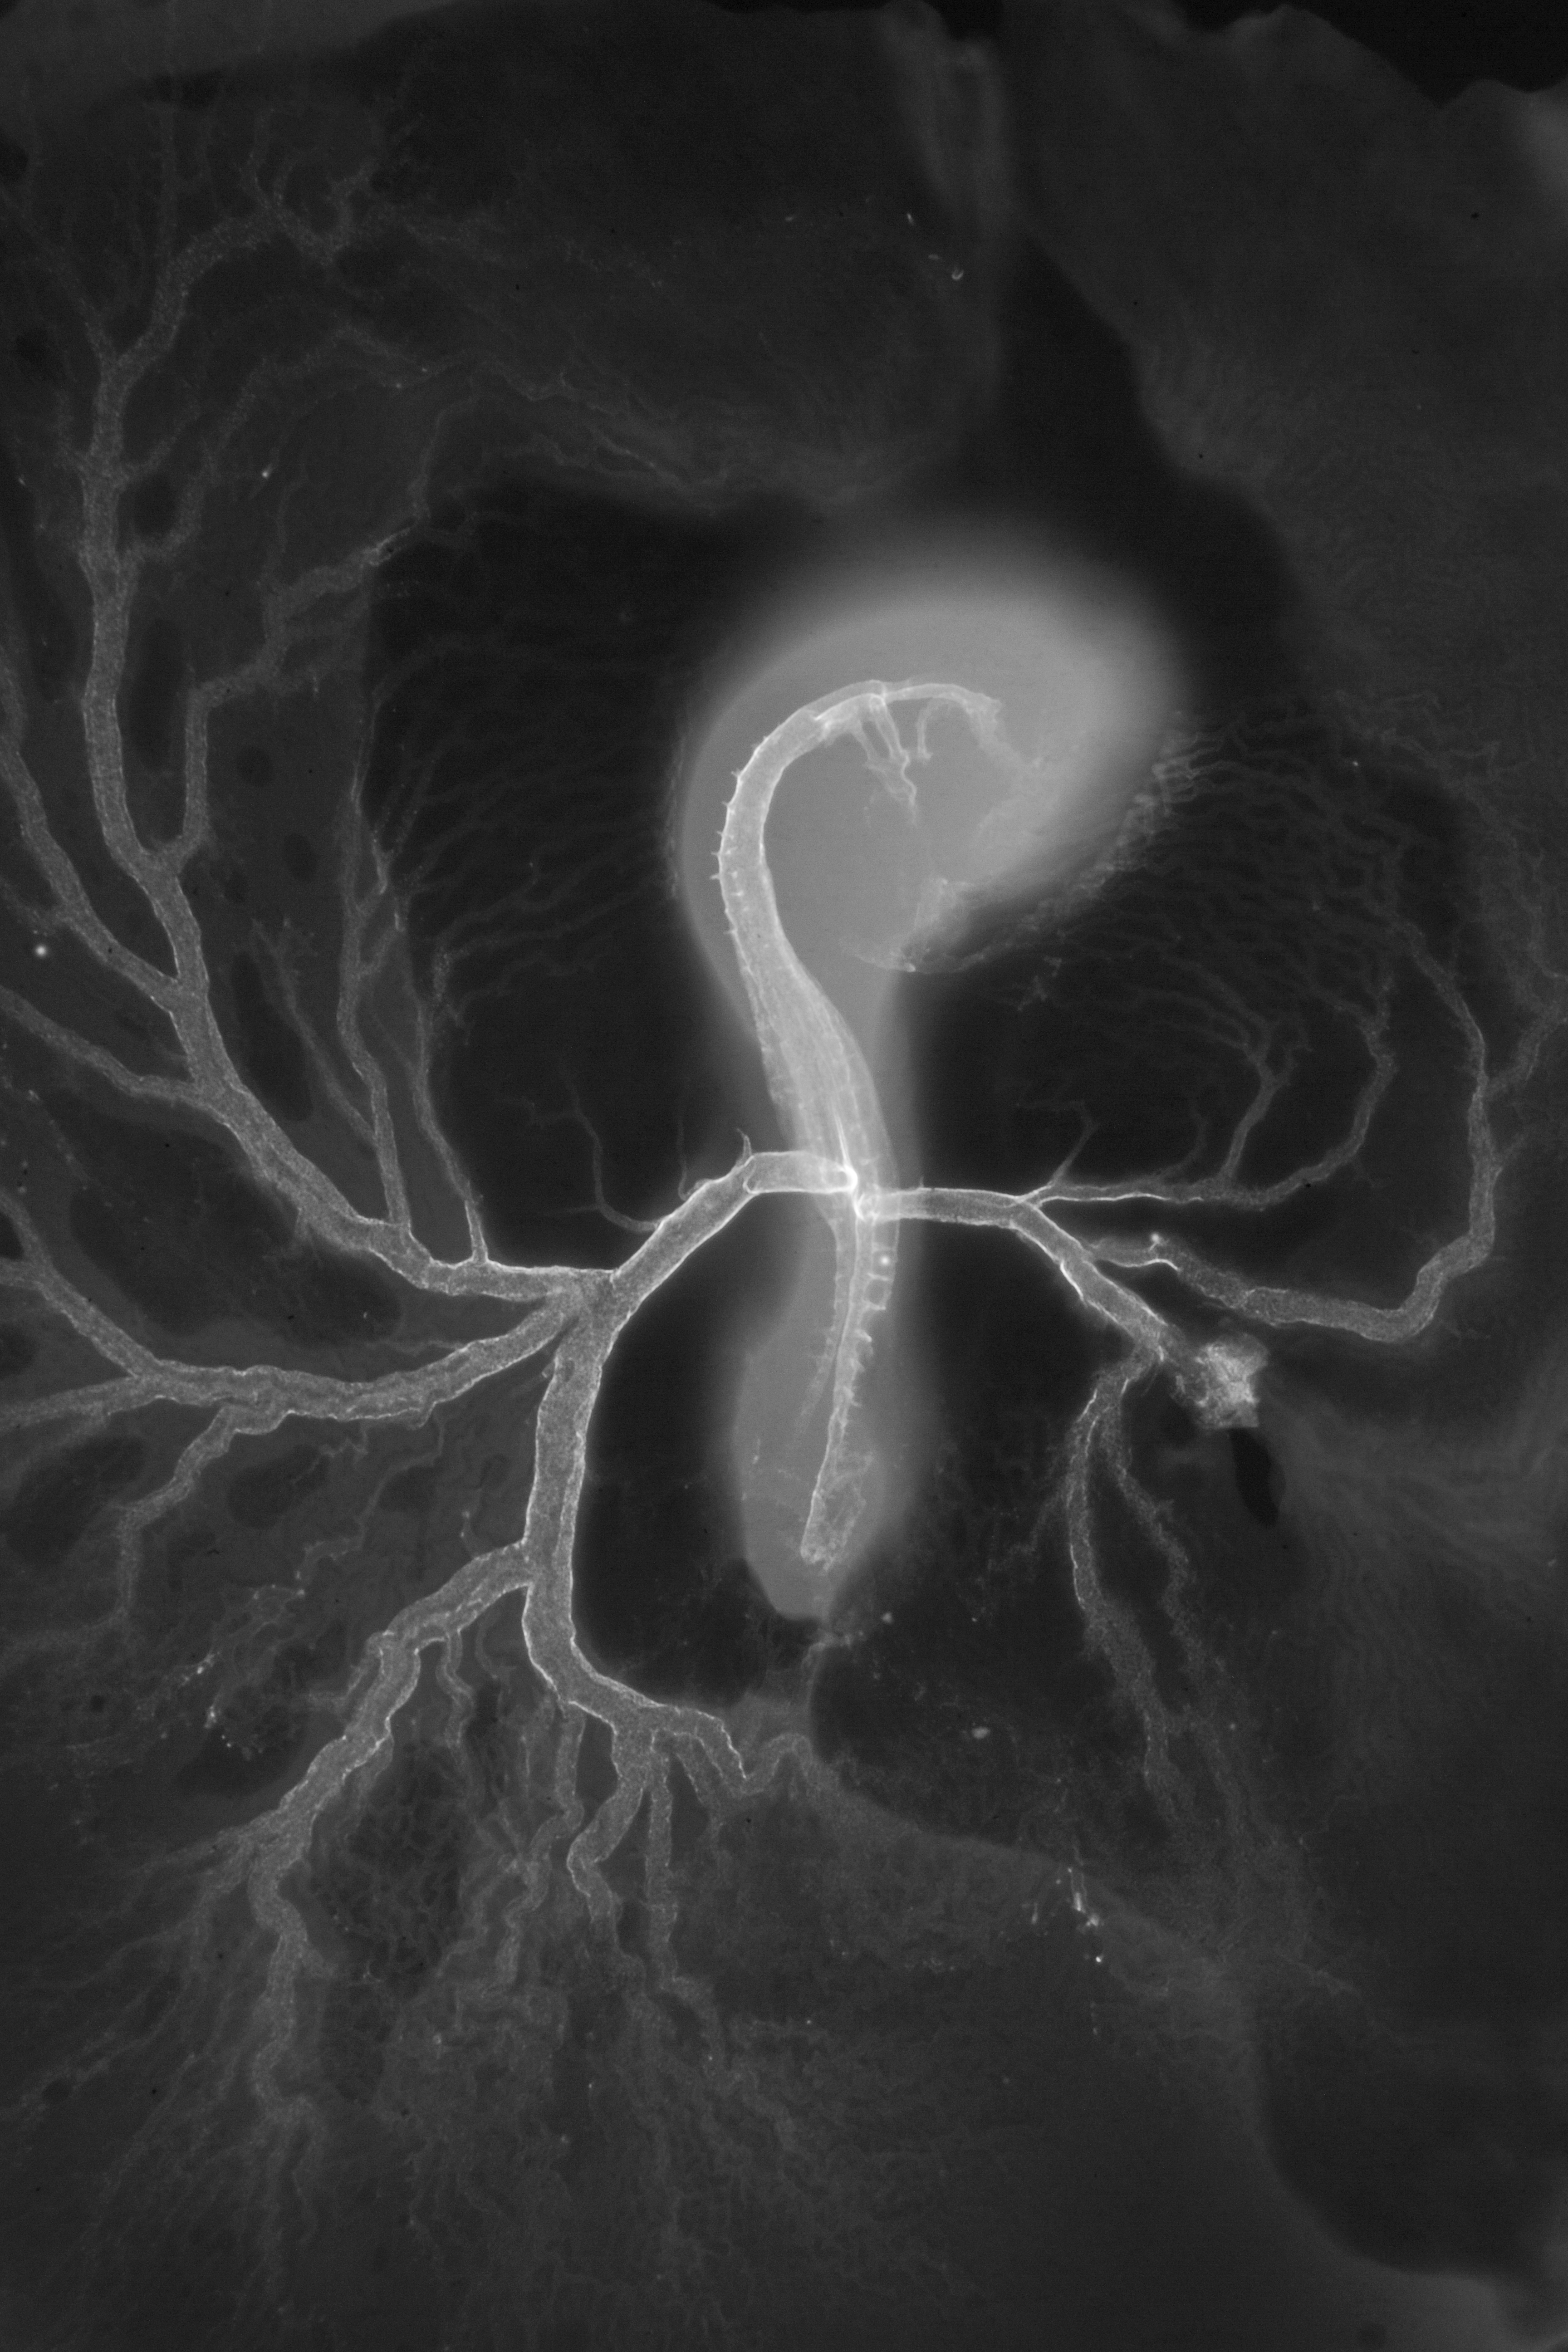

Chick Embryo Microangiography

Hamburger-Hamilton (HH) Stage 16 (approx. 2.1 - 2.5 days)

Drawing